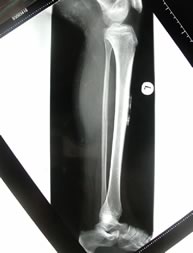

Fig 4.La calcinosi. Rx diretto che dimostra numerosi

foci di calcificazione, facilmente palpabili all'esame

obiettivo, a livello muscolare e nel sottocutaneo. La calcinosi è

generalmente una complicanza tardiva della malattia, direttamente

correlata alla durata della malattia ed ad una maggiore gravità

(della flogosi, che appunto produce la deposizione di calcio).